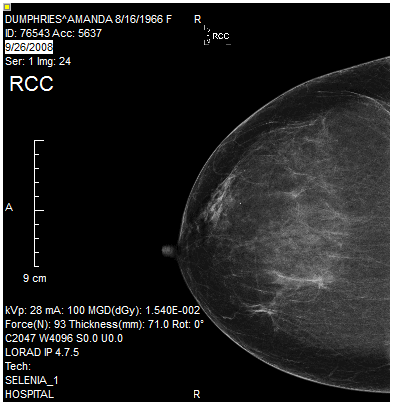

The Rotate Image 90 Degrees Clockwise tool will rotate an image 90 degrees to the right. The following example illustrates an image before and after the Rotate Image 90 Degrees Clockwise tool is applied.

After